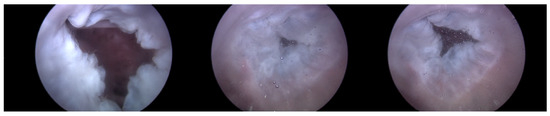

Endoscopic Image: During the experiment, the ability to adjust the intensity of TR using the TRG, as well as the changes made to the bpm, directly influenced the functionality of the TV. Real-time endoscopic imaging, as seen in Figure 6, was crucial in verifying the impact of these adjustments. This imaging technique allowed for the immediate observation of how alterations in the TR’s intensity or changes in the heart rate affected the TV’s performance. By providing a live visual feed, the endoscopic imaging enabled researchers to promptly ascertain whether the modifications being applied—either through the TRG or by adjusting the bpm—effectively influenced the valve’s operation. This real-time monitoring was essential for ensuring that the experimental conditions were accurately met and validating the immediate effects of these adjustments on the TV’s functionality.

As can be observed in Figure 8, up to a flow rate of 60 cc/min from the TRG, the TV of Heart 1 maintained its normal functionality. This was validated by the endoscopic images, as displayed in Figure 7. An induction of TR was discernible on elevating the flow rate to 70–80 cc/min; however, upon turning off the TRG, the TV reverted to its normal function. This behavior was consistent, reaffirmed by subjecting the system to the same conditions thrice, with 10 min intervals between each test. Figure 9 presents a cross-sectional view of the spectrum graph from Figure 8 during the normal phase, while Figure 10 illustrates a similar cross-sectional view but during the abnormal phase. The two figures show a noticeable discrepancy in the amplitude values between 50 and 100 bpm. Specifically, the maximum amplitude values differ tenfold, registering approximately 2.4 mmHg in the standard phase and 25 mmHg in the abnormal phase.

Figure 6. Endoscopic image of tricuspid valve function.

Figure 7. Endoscopic image of Heart 1 (valve open, normal valve closed, abnormal valve closed).